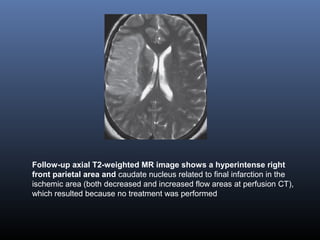

Follow-up axial T2-weighted MR image shows a hyperintense right

front parietal area and caudate nucleus related to final infarction in the

ischemic area (both decreased and increased flow areas at perfusion CT),

which resulted because no treatment was performed